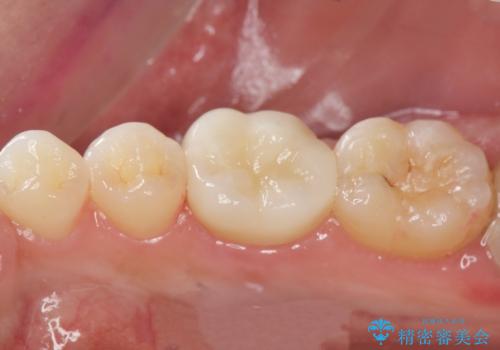

[ 深い虫歯・根管治療・セラミッククラウン ]複合した問題を持った虫歯治療

![[ 深い虫歯・根管治療・セラミッククラウン ]複合した問題を持った虫歯治療の症例 治療前](https://seimitsushinbi.jp/wp/wp-content/uploads/2022/09/b464b4c5c3053a5fc84212fb664a039f-500x350.jpg?v=1663667230)

![[ 深い虫歯・根管治療・セラミッククラウン ]複合した問題を持った虫歯治療の症例 治療後](https://seimitsushinbi.jp/wp/wp-content/uploads/2022/09/bd017e5dbd742f9bb33f09d39c8f1b52-500x350.jpg?v=1663667487)